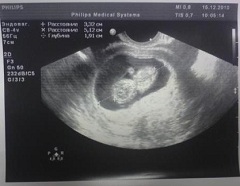

Обычно УЗИ на 10 неделе беременности назначают всем женщинам в качестве скринингового исследования. При нормально протекающей беременности - это первое ультразвуковое исследование плода, по его результатам судят о количестве плодов, их движениях и сердцебиениях, о грубых аномалиях и пороках развития. Обнаружение пороков плода, несовместимых с жизнью, на таком раннем сроке беременности может стать показанием для ее прерывания. УЗИ на 10 неделе беременности подтверждает жизнеспособность плода и уточняет срок гестации.